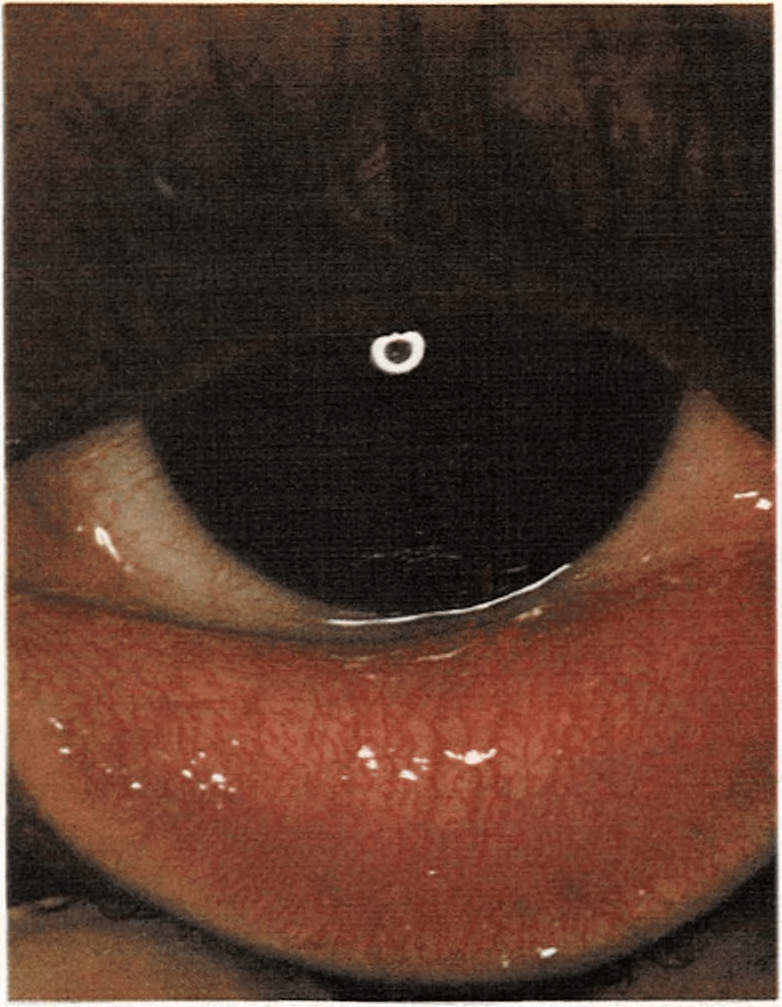

Conjuntivitis

Es la inflamación de la membrana mucosa que recubre el polo anterior del ojo y la parte posterior del párpado y es producida por bacterias, virus o irritantes químicos como el humo o el jabón. Generalmente aparece aislada, pero en algunas ocasiones se manifiesta en los resfriados, sarampión, varicela y otras enfermedades.

Cuando un niño se queja de que tiene “algo en el ojo” puede tratarse de una conjuntivitis. Este es uno de los primeros síntomas, seguido de lagrimeo, légañas con pus, hinchazón, escozor, quemazón y gran molestia causada por la luz. Los síntomas son más intensos por la noche, después de la actividad de todo el día variando según el grado de inflamación sufrido. Por la mañana, los párpados del niño pueden estar pegados por légañas que se han secretado durante la noche. Se lavarán los ojos con agua, una vez abiertos, pero no se usará ningún otro tratamiento casero. Si la inflamación no se cura en poco tiempo, se consultará con el médico. La conjuntivitis no siempre es contagiosa.

Véase también Alergia; Ojos, salud de los